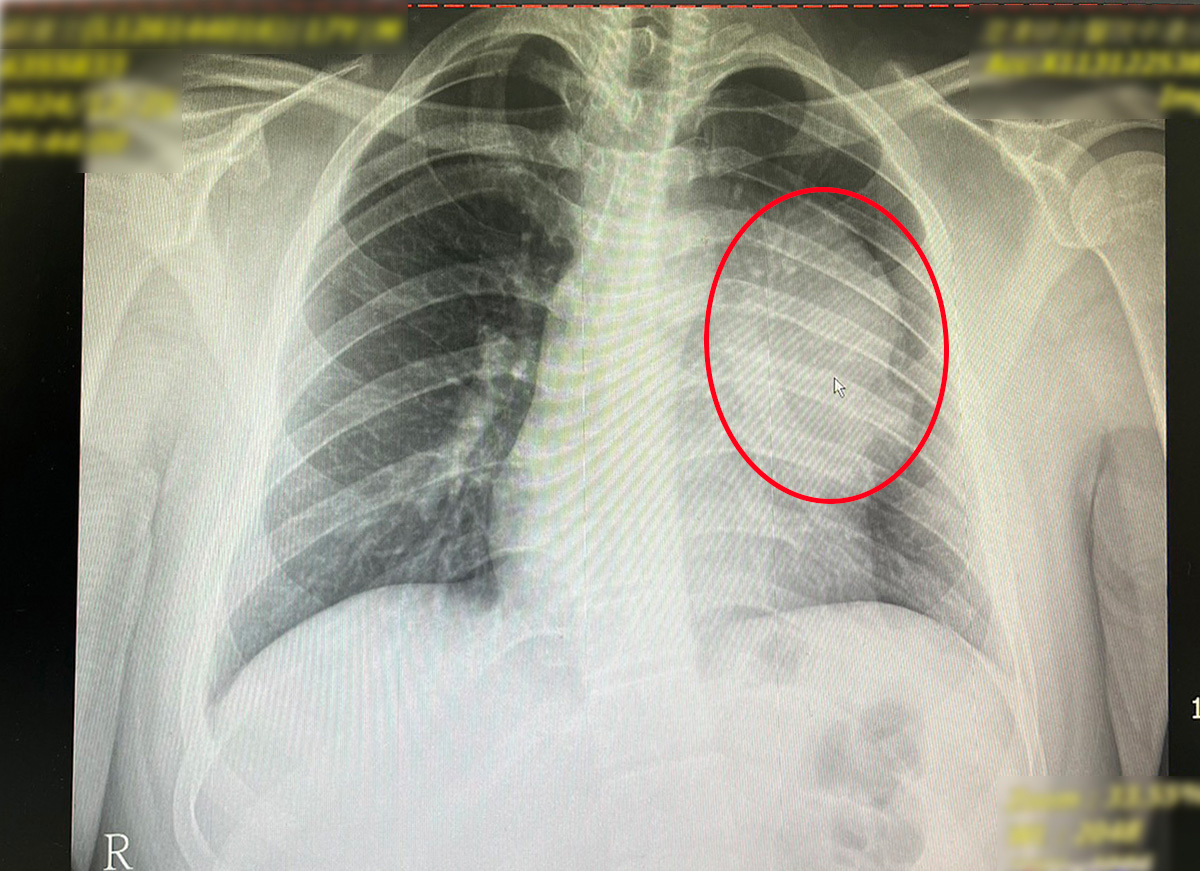

這位17歲少年外表高壯、平時毫無任何不適症狀,但在學校健檢的胸腔X光中卻發現肺部陰影。於2022年12月接獲通知後,立刻轉診到澄清醫院中港分院胸腔外科就診。胸腔外科賴重佑部主任表示,在前縱膈腔偏左側發現了約12公分且高度懷疑為惡性的腫瘤,須進一步檢查釐清。

為了確定腫瘤的性質及與周邊器官的黏著程度,院方先進行切片以辨別是否為淋巴癌或其他病變,同時安排胸部核磁共振造影,以排除腫瘤侵犯心包膜的可能性;亦檢查腫瘤與心臟、肺臟的黏著情況。考量該腫瘤疑似生殖細胞瘤,團隊也進行腹部電腦斷層掃描,最終確診為「縱膈腔精細胞瘤」。